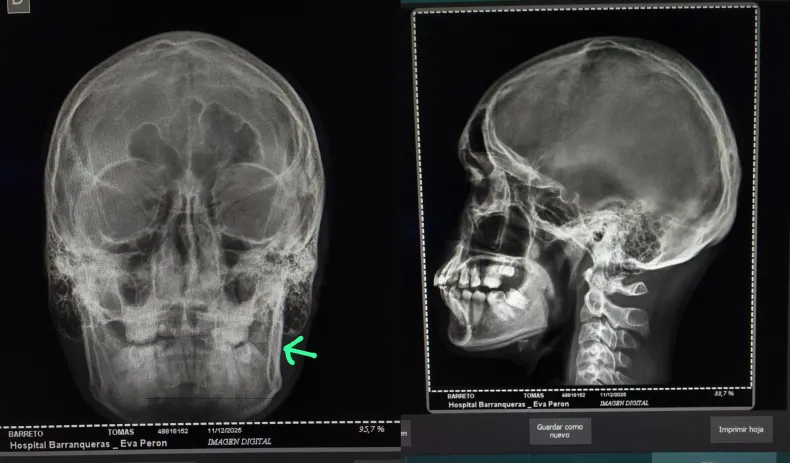

Como consecuencia de la agresión, el joven sufrió la fractura de la mandíbula, tres dientes flojos y múltiples golpes en el cuerpo y la cabeza. Además, la mujer denunció que el agresor también atacó a otro menor que intentó defender a su hijo.